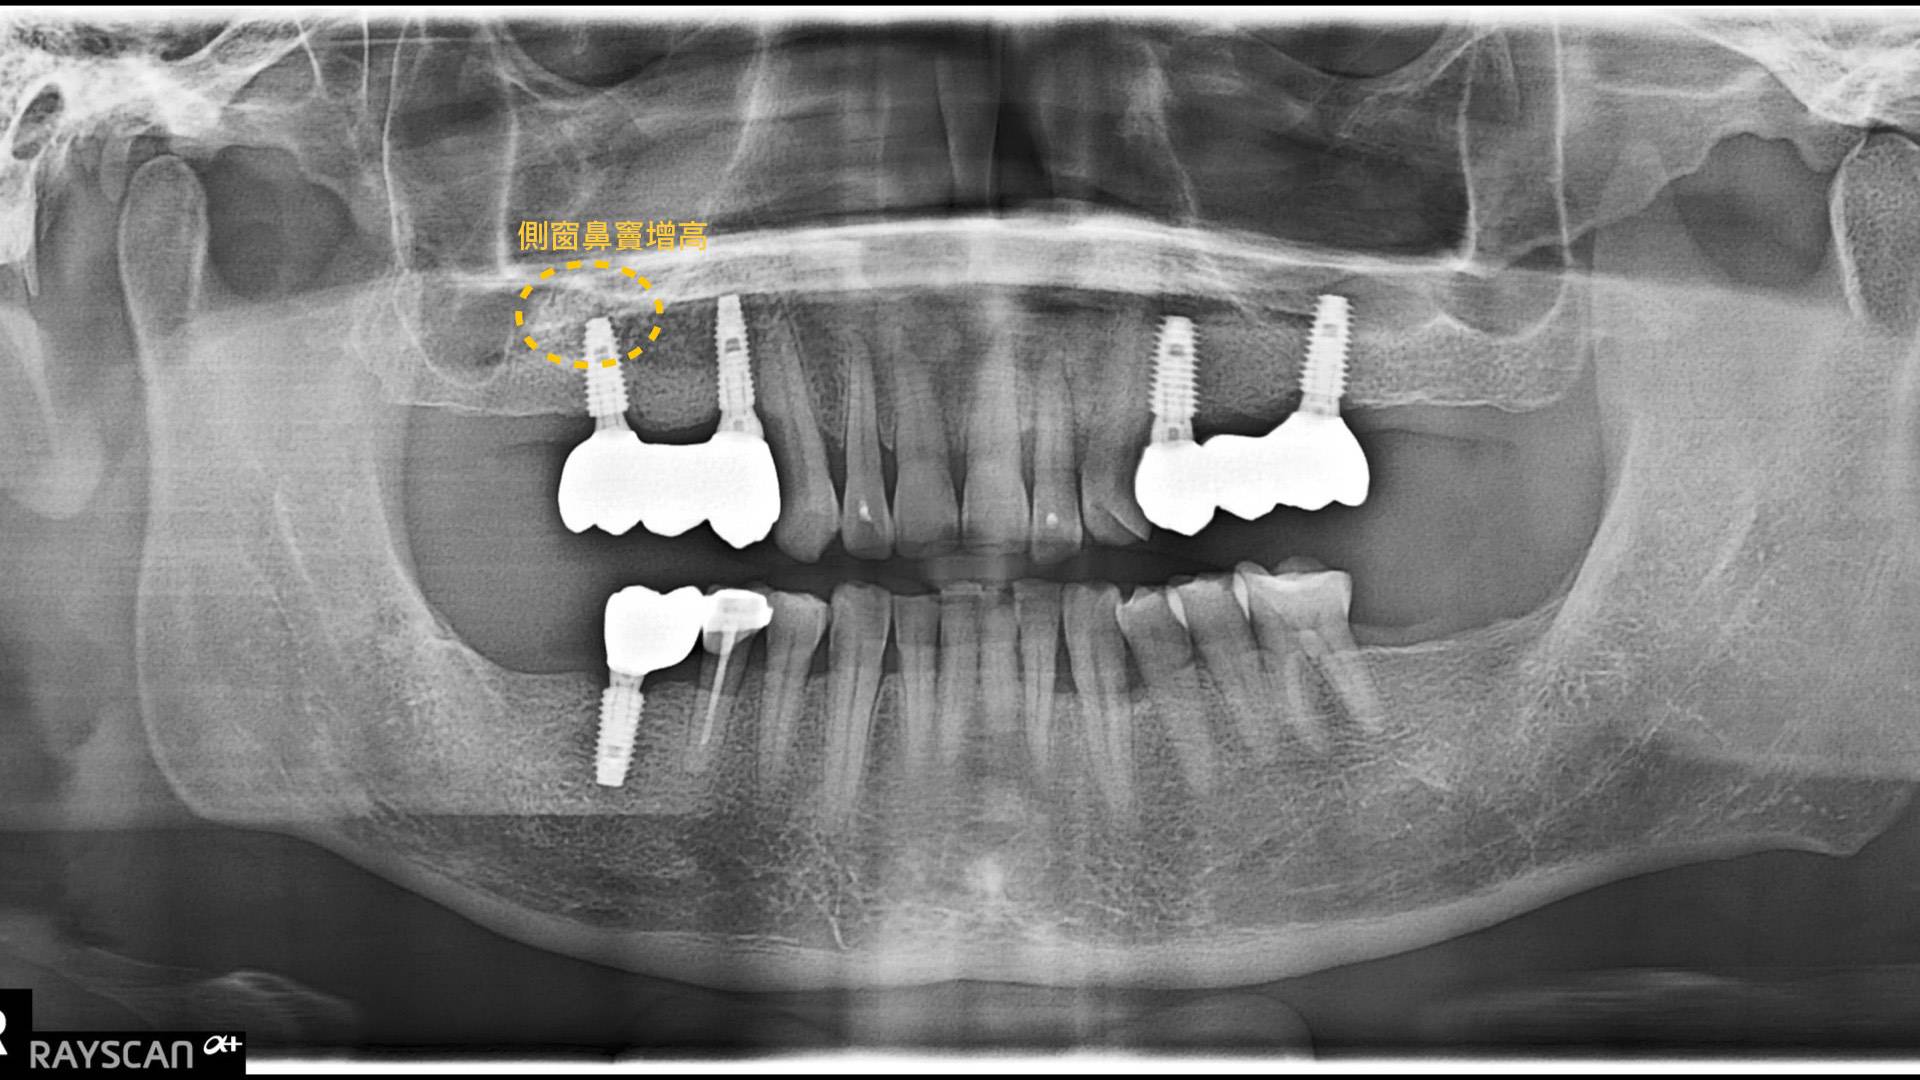

植牙重建合併側窗鼻竇增高 FT.江松岳醫師

此案例利用植牙建立病人缺牙區的咬合。右上後牙區域齒槽骨高度不足且鄰近鼻竇,採取側窗鼻竇增高術後植牙。